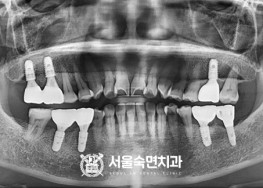

임플란트-치료-전후사진